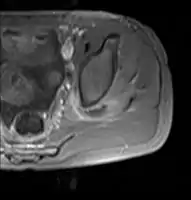

Axial T1 weighted fat suppressed post IV gadolinium contrast enhanced MRI image showing a mutliloculated bacterial abscess in the left gluteal muscle which grew Staphylococcus aureus (methicillin sensitive) thought to be due to tropical pyomyositis. Axial T1 weighted fat suppressed post IV gadolinium contrast enhanced MRI image showing a mutliloculated bacterial abscess in the left gluteal muscle which grew Staphylococcus aureus (methicillin sensitive) thought to be due to tropical pyomyositis.